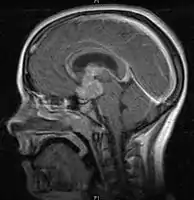

- Mainly located in midline structures, suprasellar region or pineal gland, also basal ganglia and hypothalamus

- Bifocal germinomas (synchronous suprasellar and pineal tumors) regarded as M+ in USA but M0 in Europe

- Pineal Gland Germinoma

- Suprasellar Germinoma